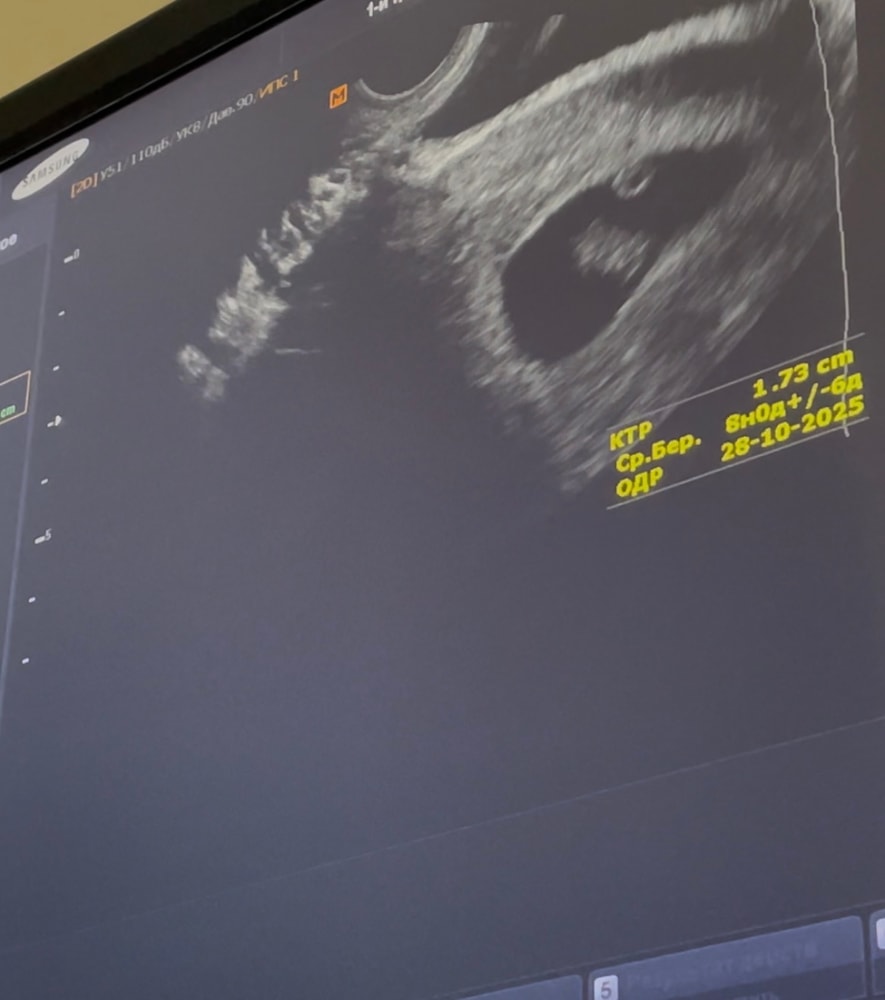

Автор вот двойня однояйцевая на сроке 8 недель Изображение

На снимке один эмбрион 17,3 мм на срок 8 недель и рядом желточный мешочек,на таком сроке и второй если бы бы то +- такого же размера и его бы точно разглядели,непонятно что врач не может понять

Такой себе узист который не может понять. На снимке 1 эмбрион и рядом ЖМ

Посему вы думаете про двух? На снимке один эмбриончик и жм рядом. Узист бы увидел уже, если бы было двое

На этом снимке 1 эмбрион

Один эмбрион и мешочек